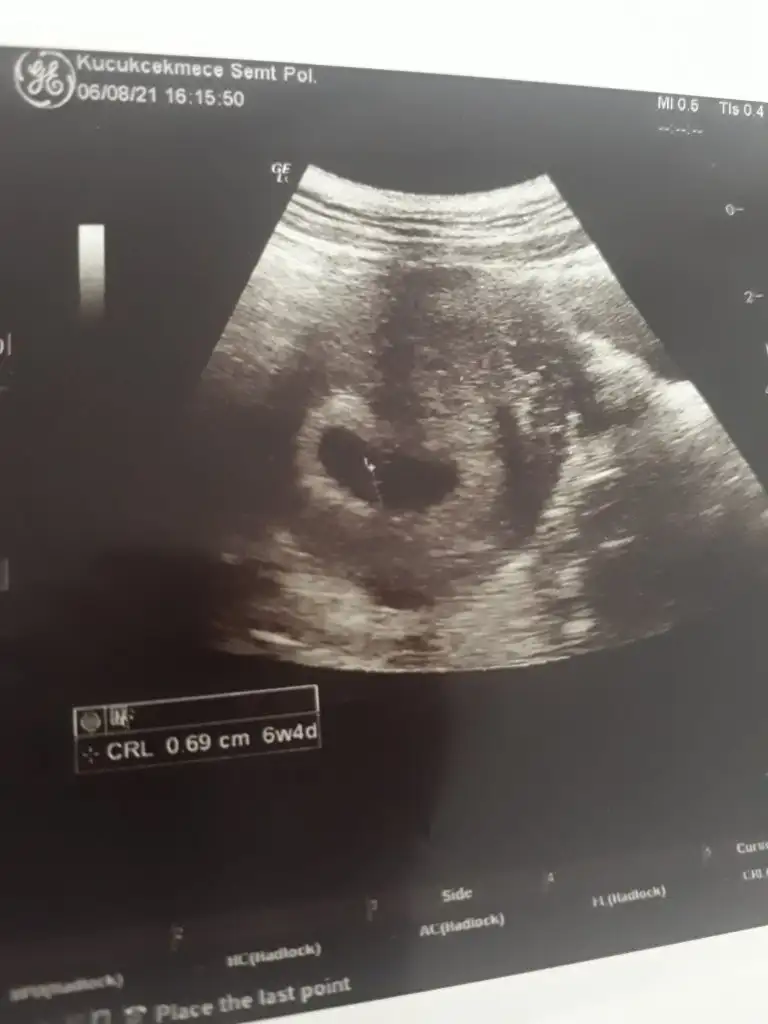

Merhaba, buna da bakabilir misiniz?

Eklentiler

• E3C9A60B-4827-4BD8-894A-C457D9F413B4.webp

E3C9A60B-4827-4BD8-894A-C457D9F413B4.webp

33,4 KB · Görüntüleme: 84